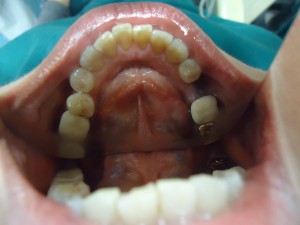

40代女性:左下の奥から3番目の歯を抜いた後、何もいれずにそのまんまになっています。

上から見るとこんな感じになっています。

本来なら、両隣の歯を削ってブリッジにするか、インプラントにするか、あるいは1本だけの入れ歯を入れるか・・ということになります。

でも、入れ歯はなんとなく抵抗があるし、インプラントもイヤ、隣の歯は健康な歯とセラミックの歯なので削ってブリッジにするのもイヤ・・・。

・・・というわけで、ウェルデンツにしました。

両隣の歯は一切削らないので、麻酔さえ不要。

型をとるだけなので、痛みもありません。